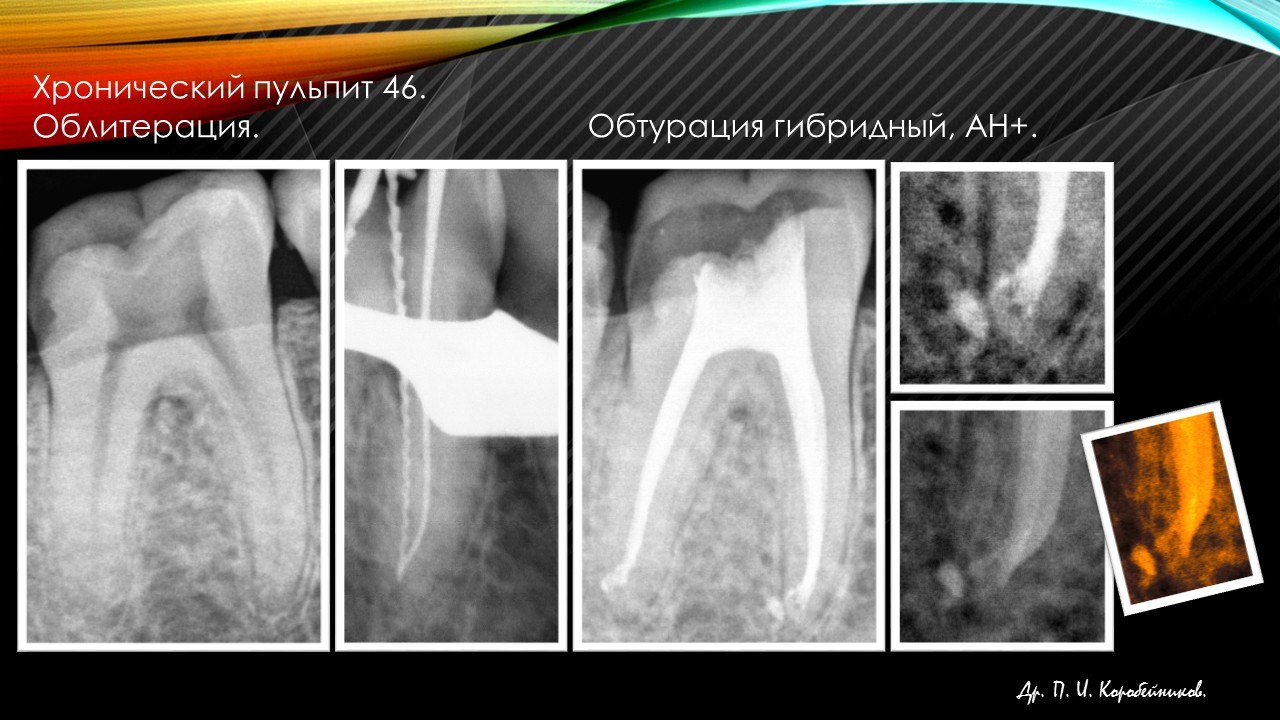

Стоматолог- эндодонт, стоматолог- терапевт, стоматолог- ортопед, стоматолог- хирург.

Работа с микроскопом, консультации и лечение пациентов, эндодонтия, терапия, ортопедия, хирургия(в небольшом объеме).